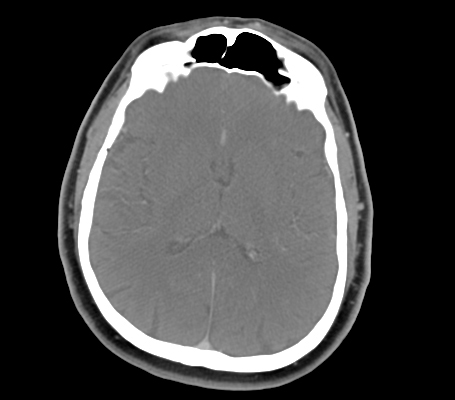

• Frontal Sinus

• Temporalis Muscle